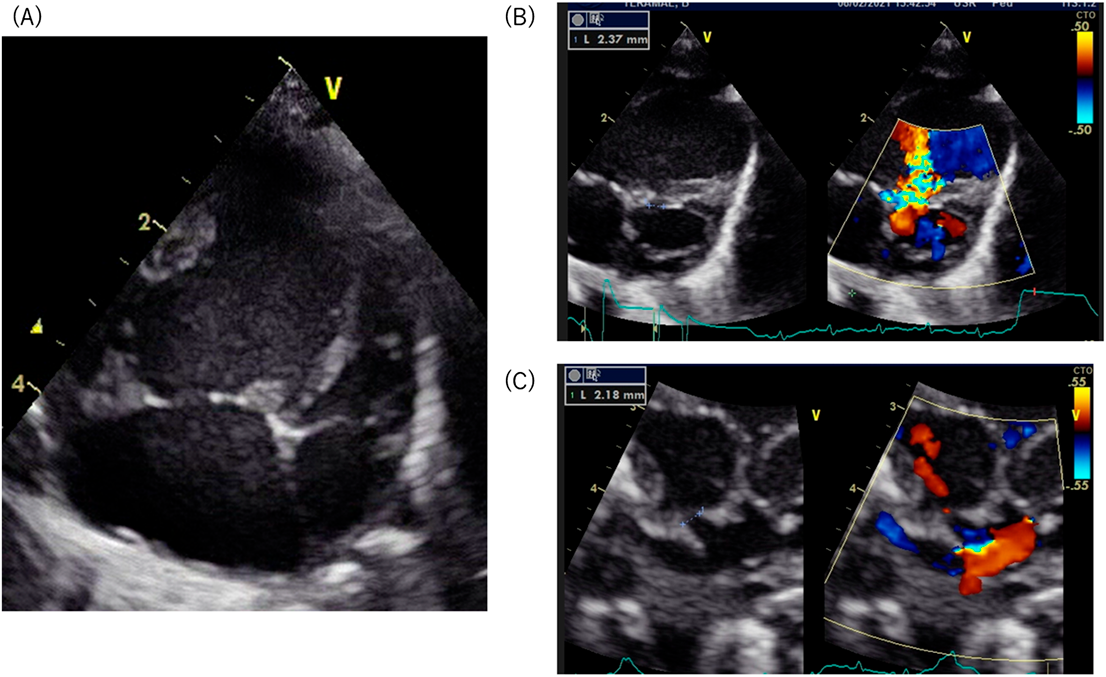

Fetal echocardiography was performed at 33 weeks of gestation at our institution, identifying a form of hypoplastic left heart syndrome with restrictive foramen ovale. The male infant was born at 38 weeks gestation via planned cesarean section, had an oxygen saturation of 89% on room air. A transthoracic echocardiography confirmed diagnosis of mitral stenosis, aortic stenosis, a small ventricular septal defect and restrictive foramen ovale (Fig. 1A–C). The four pulmonary veins were visualized, connecting to the left atrium. This patient was considered to be a candidate for the Fontan circulation in the future. Pulmonary congestion was not observed immediately after birth. We expected that pulmonary congestion should progress due to the restrictive inter-atrial communication when physiological pulmonary hypertension would decrease. This neonate underwent a balloon atrial septostomy at 1 day of age, followed by bilateral pulmonary artery banding at 2 days of age. Before performing the Norwood procedure, catheter investigation was carried out at 18 days old. This examination revealed step up of oxygen saturation at the superior vena cava; the oxygen saturation was 66%, 83%, and 93% at the inferior vena cava, the right atrium, and the superior vena cava respectively. We suspected a collateral vessel connecting the pulmonary vein to the systemic vein. Angiography of the left atrium revealed an abnormal vein draining to the innominate vein (Fig. 2A, Suppl Movie1). 3D contrast-enhanced computed tomography also showed this vein connecting the left pulmonary vein to the innominate vein (Fig. 2B, C). The abnormal vessel was identified as a levoatrial cardinal vein. The Norwood procedure was performed without ligation of this abnormal vessel. Enlargement of the atrial septal defect was performed simultaneously to avoid pulmonary congestion. The postoperative course was uneventful with no pulmonary venous obstruction.

Fig. 2 (A) Angiography showing the levoatrial cardinal vein draining to the innominate vein. (B) 3D contrast-enhanced computed tomography viewing from the front illustrates the levoatrial cardinal vein connecting the left pulmonary vein to the innominate vein. (C) 3D contrast-enhanced computed tomography viewing from the left-posterior aspect shows the levoatrial cardinal vein connecting the left pulmonary vein to the innominate vein.

Red arrows indicate the levoatrial cardinal vein.